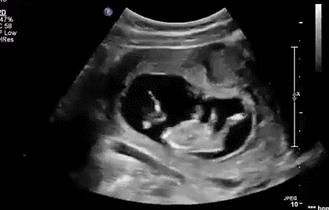

等到他再大点的时候,“蛙泳”项目已经无法进行了,但是你以为他长大点了就会听话、懂事,当个乖宝宝吗?

可不会。

咦?这地儿怎么越来越小了,不管,我挤,我顶......

▼

顶了这么久,“房子”怎么还是这么小?

管他呢,我要出去,我要游泳,我继续蹬腿,我蹬……

哇,看到没有!我的大长腿是不是很迷人!